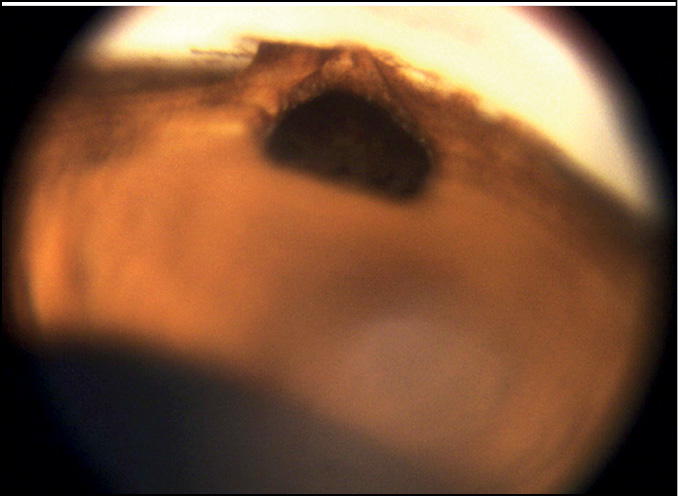

Анализ гониоскопического состояния области ВФ — области склерэктомического окна, иссечённого при ТЭ — показал (табл. 1), что среди вариантов заращения ВФ преобладал частичный блок ВФ (75,3%) (рис. 1), а полный блок ВФ наблюдался только в четверти случаев (24,7%) (рис. 2).

Рис. 1. Частичный блок внутренней фистулы.

Рис. 2. Полный блок внутренней фистулы.